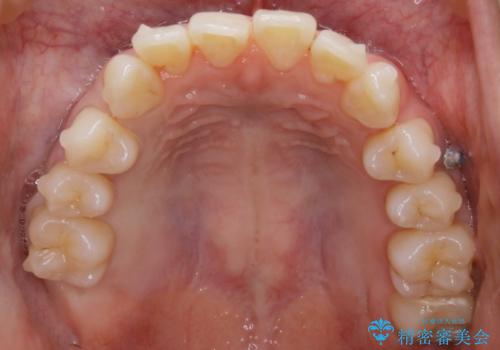

- 笑った時の歯の見え方を治したいとのことで矯正相談にいらっしゃいました。

一見そこまで大きなガタつきはないようにも見えますが、前歯の角度の不揃いや噛み合わせのズレなどから見え方に影響が出てしまっていました。

抜歯は全く必要のないレベルのガタつきだったため、マイクロインプラントを用いて歯全体を後方に移動させていくことできれいな歯並びを獲得することができました。

マウスピースとマイクロインプラントを組み合わせることで、抜歯をしなくても歯並びを治すためのスペースを作ることができます。奥歯から順に移動させていくので前歯に変化が出るまでには時間がかかりますが、どの分健康な歯を抜歯することなく理想的な歯並びを手に入れることができます。